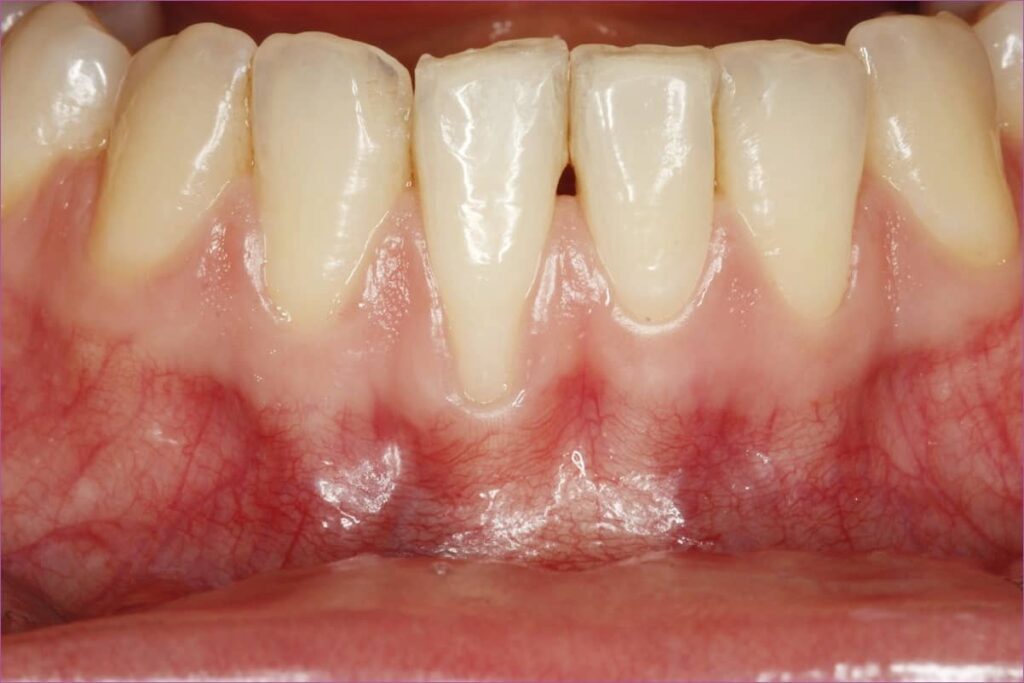

A gyógyulás eseménytelenül zajlott. A varratokat 2 héttel műtét után lehet eltávolítani, ez alatt az idő alatt a pácienst 3 alkalommal hívtuk vissza kontrollra. A műtét sikerességét az első 2 hét gyógyulási idő nagymértékben befolyásolja, amennyiben ez alatt az idő alatt bármilyen ártalom éri a műtéti területet, az átültetett kötőszövet elhalhat és felszívódhat. Ezért az ínyrecesszió kezelésének utolsó fázisának tekintett időszak során 2 héten keresztül nem szabad fogat mosni a műtéti területen, valamint tilos harapni-rágni a frontfogakkal. Helyette a hátsó őrlőfogakat kell használni étkezésnél. Kerülni kell az alsó ajak mozgatását, vagyis 2 hétig nem szabad túlzottan artikulálva beszélni. Mivel a páciensünk szigorúan betartotta az instrukciókat, sikerült az ínyt közel tökéletes pozícióba visszaépíteni és a fognyaki érzékenység is nagymértékben javult. A páciens rendkívül elégedett volt az elért eredménnyel, hiszen az ínyrecesszió kezelése sikeresnek bizonyult.

ínyrecesszió kezelés utáni állapot